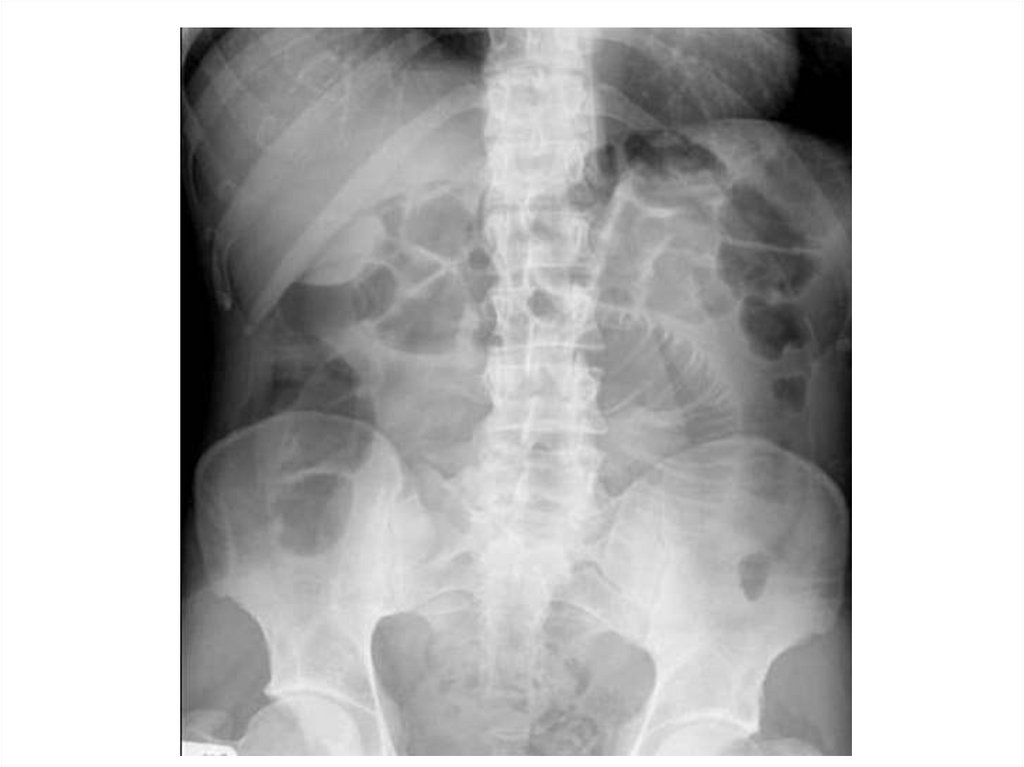

Назовите

• Вид исследования

• Область исследования

• Патологию